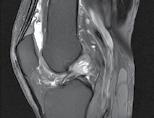

Se practică radiografii standard, examinare CT sau RMN.

CT-ul cu reconstrucție tridimensională sau RMN genunchi relevă mult mai

bine complexitatea fracturii și dau posibilitatea unui planning preoperator superior estimării radiologice clasice(7). CT-ul este mai rapid și mai ușor de făcut, dar RMN decelează mai bine leziunile de menisc sau ligamentare.

În fracturile Schatzker I, fără leziuni de menisc extern asociate este indicată reducerea și osteosinteza percutană cu șuruburi. Dacă leziunea de menisc este evidențiată pe RMN, se poate opta pentru reducere și osteosinteză percutană cu șuruburi asociată cu artroscopie(12), având rol de control al reducerii și curativ pentru leziunea de menisc, sau reducere deschisă și fixare internă cu placă și șuruburi.

La pacienții tineri cu fracturi Schatzker tip II și III se poate opta pentru reducere și osteosinteză percutană cu șuruburi asociată cu artroscopie. O altă variantă este cu grefă osoasă și reducere deschisă cu fixare internă cu placă și șuruburi. Controlul reducerii intraoperator se realizează artroscopic sau cu C arm.